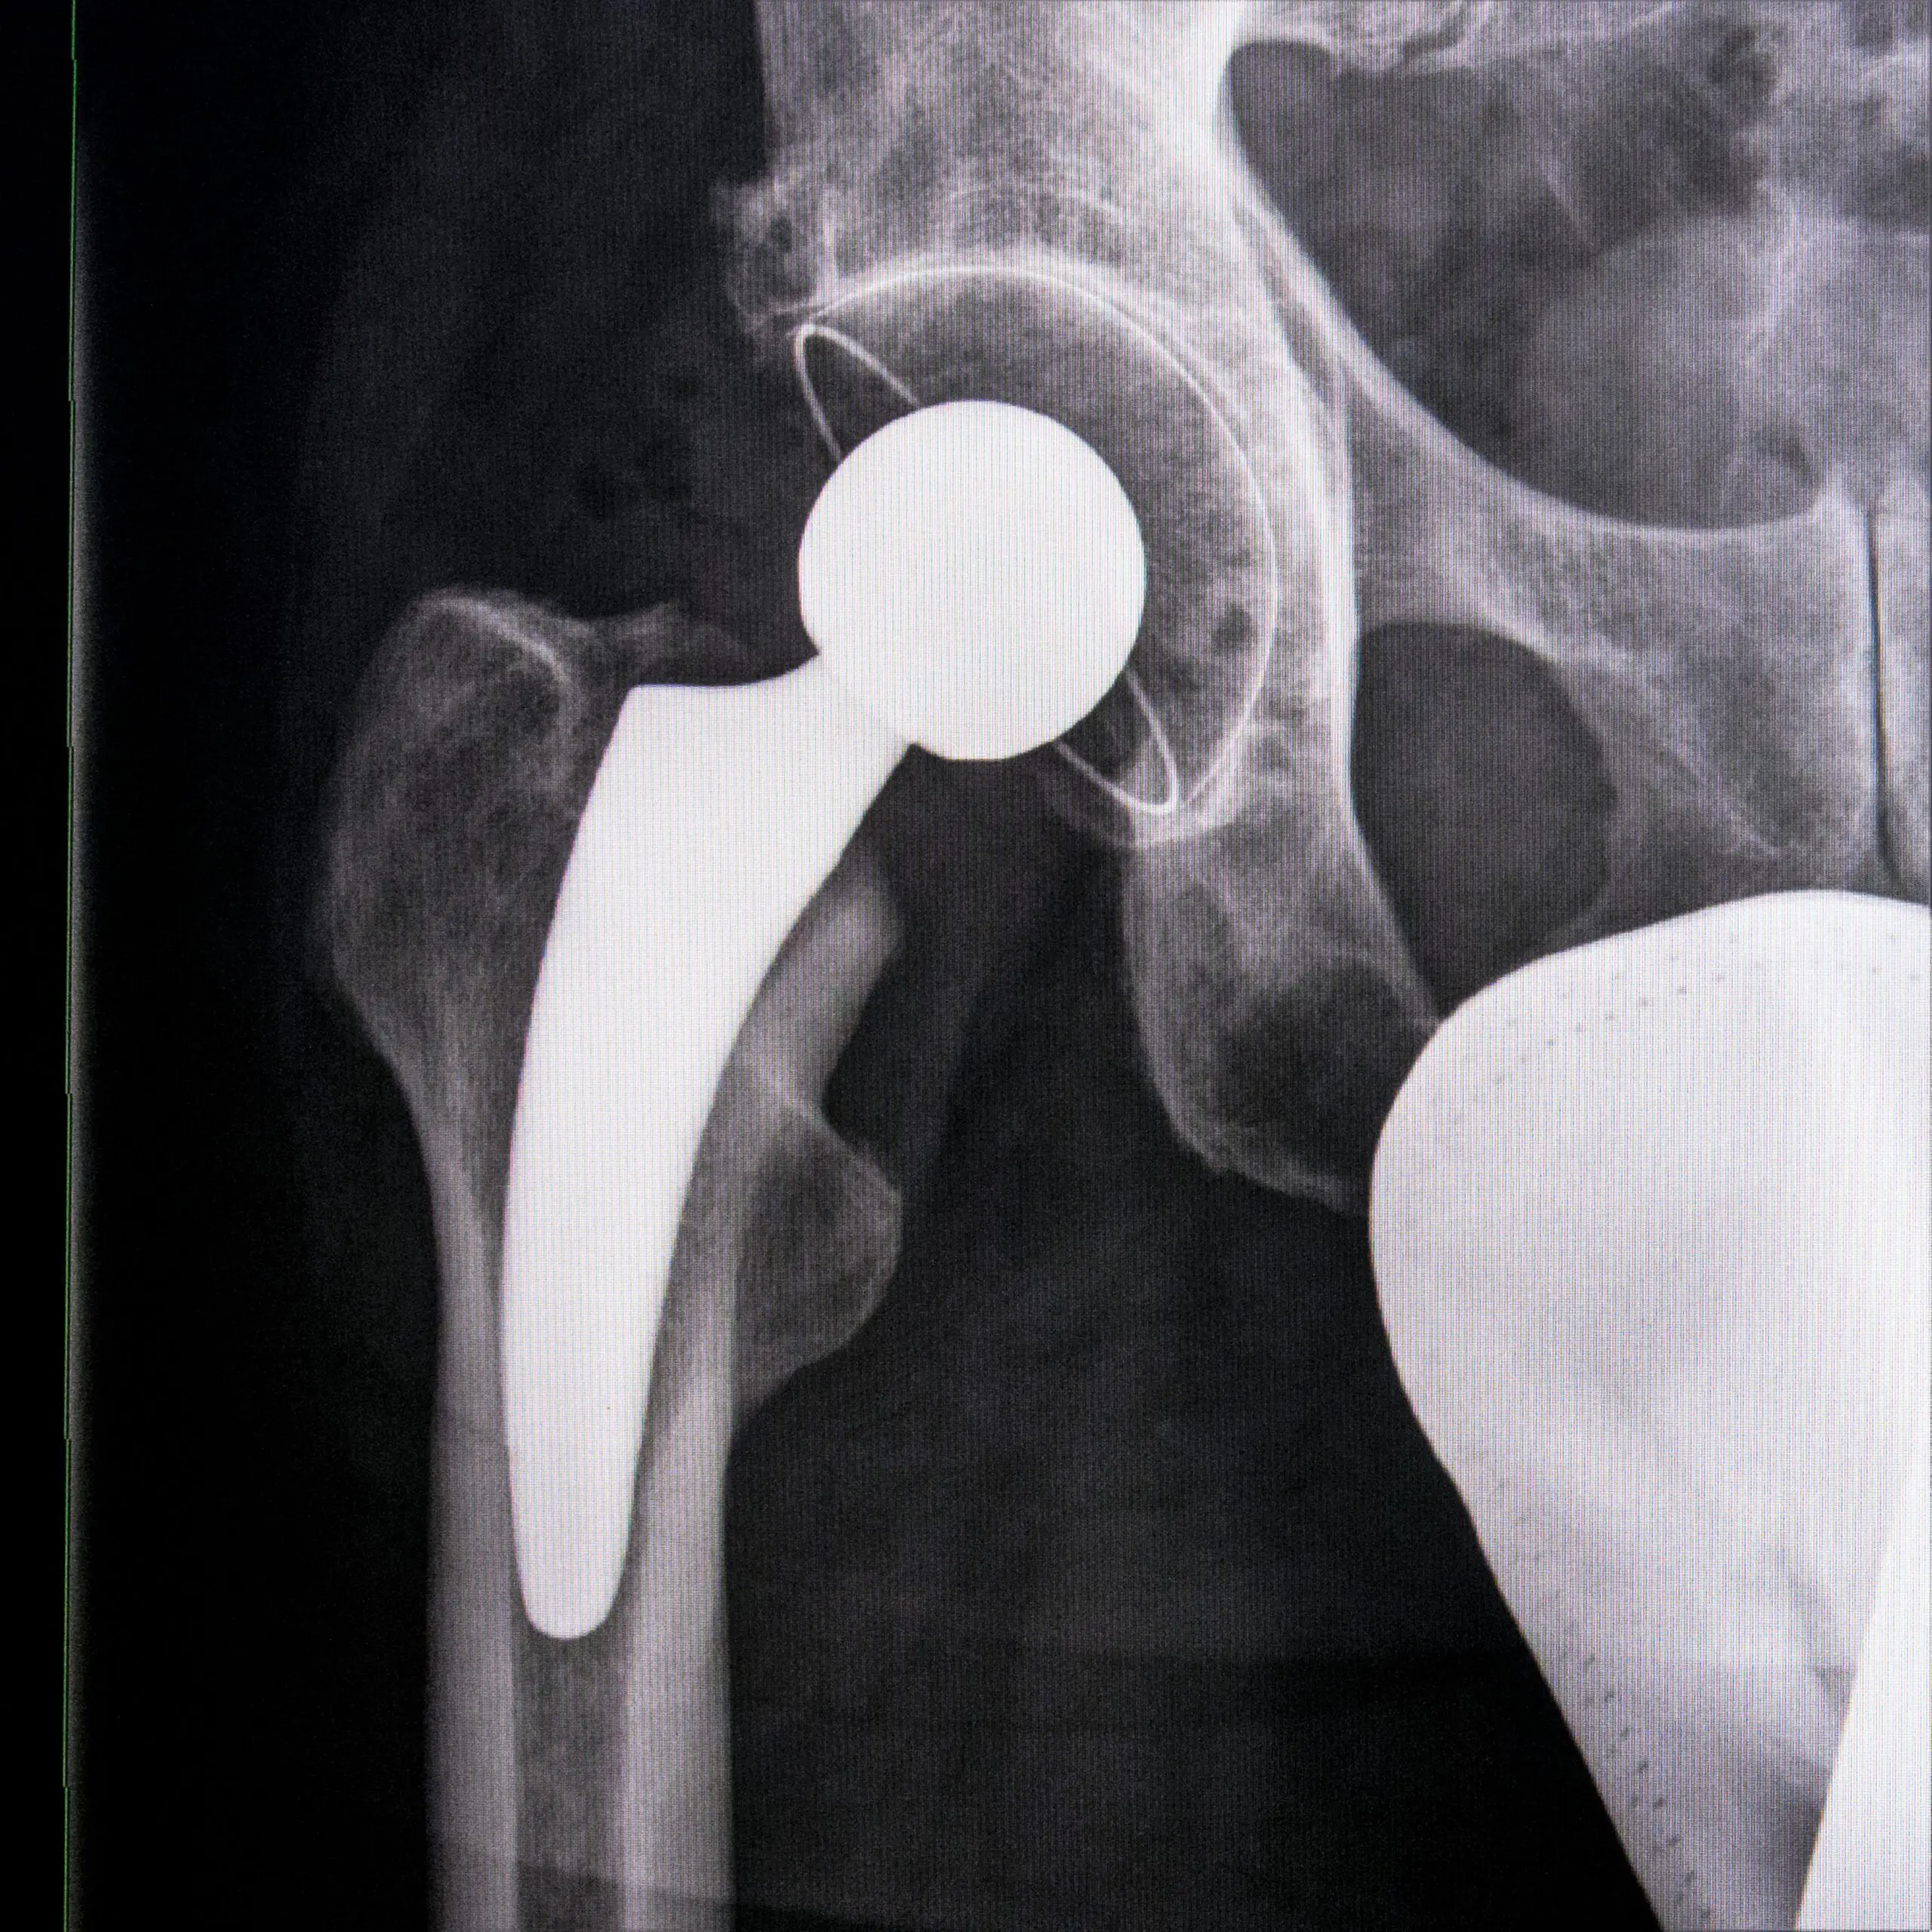

Свива се ставната капсула и мускулите захванати до нея, което води до непроизволно сгъване на крайника и невъзможност за обръщане навътре. Мерките при лечението на коксартроза са забавяне процеса на износване и необходимостта от подмяна на ставата да бъде отложена значително.

Как се лекува коксартроза

За лечението на коксартроза още при първите оплаквания – заповядайте в МЦ,,Орто Пункт’’ в София, където работят специалисти с дългогодишен опит. Ще бъдете посрещнати с внимание и човешко отношение.

Целта е подпомагане на възстановителните възможности на организма и забавяне максимално разрушителните процеси. Основен фактор за цялостното лечение и превенция на коксартрозата е поддържането на нормално тегло. Качването на телесно тегло е пагубно за болната става.